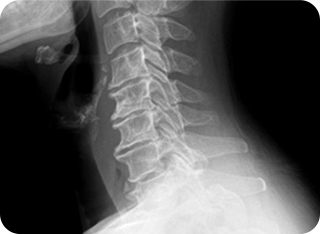

X-ray 검사 장비1

1

환자 증상, 증후 진단 및 X-ray 검사

우리가 흔히 아는 기본적인 검사는 환자의 병력 · 증상 · 신경학적 검사, 이학적 검사 그리고 척추의 배열 상태를 보는 역동적 방사선 촬영입니다. X-ray 검사는 척추 뼈, 디스크를 포함한 관절 부분의 퇴행 정도, 척추의 측만증이나 후만증 여부, 그리고 실제 굴곡과 신전시 척추의 불안정성을 진단하는데 있어서 매우 중요한 검사입니다.